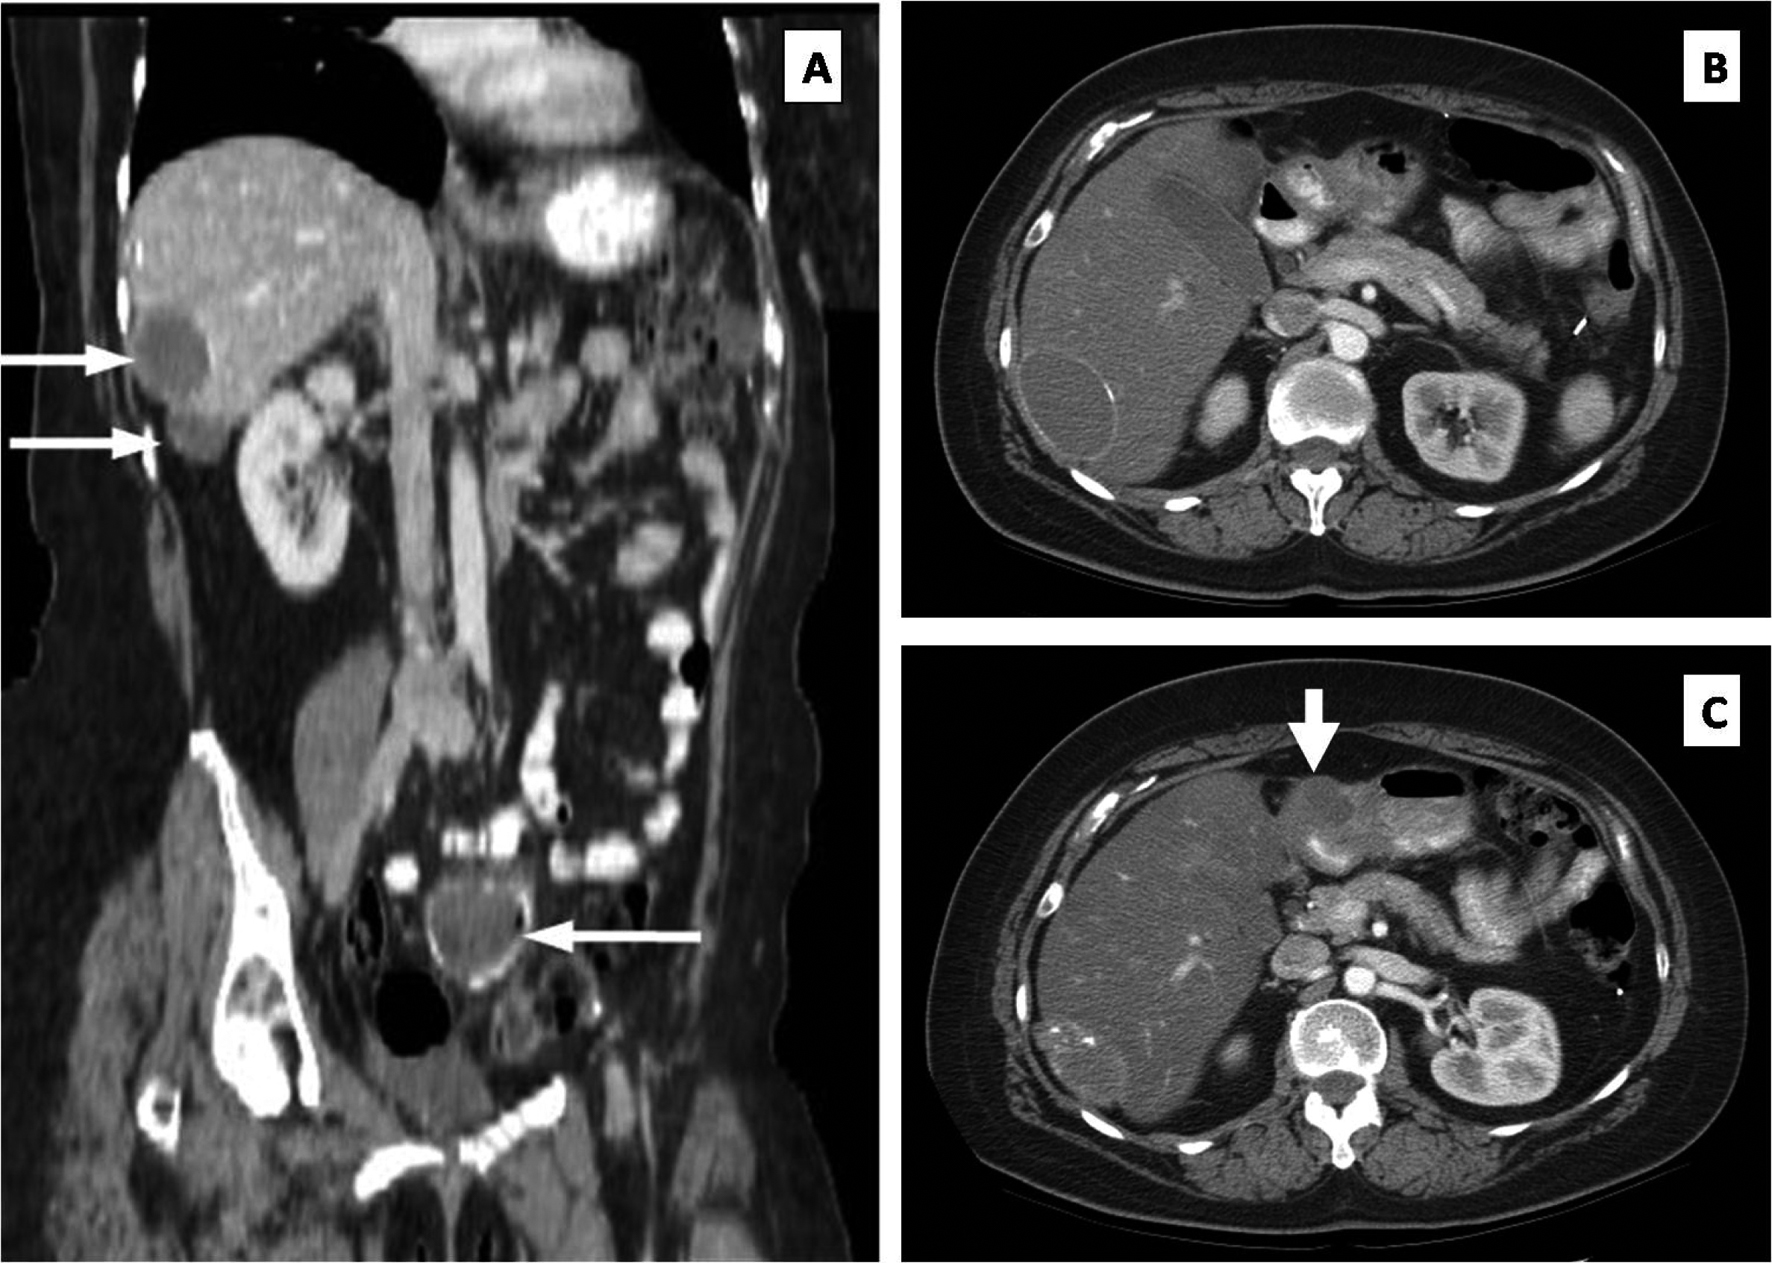

In 1997, the patient underwent pelvic tumor debulking and excision of multiple invasive peritoneal implants for recurrence. At the completion of the operation, no gross evidence of disease was seen. In the years following, she was treated with a variety of chemotherapeutic regimens including agents such as altretamine, etoposide, and gemcitabine, which were met with a variety of ultimately limiting side effects. She finally started treatment with vinorelbine (Navelbine) in April 2001 and tolerated this medication well. Surveillance computed tomography (CT) in 2003 once again revealed evidence of pelvic recurrence in addition to two surface liver masses consistent with peritoneal implants, which are seen in the coronal CT cuts shown in Figure 1A (thin white arrows). Close clinical and radiologic follow-up demonstrated a stable appearance of the pelvic mass and no change of either liver mass upon approaching her 94th cycle of vinorelbine in February 2009. Her CA-125 level ranged from 34.3 to 86.7 U/mL during this period of latency.

![]() Click for large image | Figure 1. (A) Stable liver metastases (upper white arrows) and pelvic metastasis (lower arrow). (B) Axial CT showing no obvious peritoneal mass at the pylorus. (C) Repeat axial CT performed one year later documenting a new mass (thick white arrow) at the level of the pylorus. |

One month later, the patient presented with lower abdominal pain and CT evidence of extraluminal air within the pelvic tumor consistent with super-infection from an adjacent rectosigmoid perforation. She underwent a sigmoid colectomy with additional cytoreduction and completion omentectomy. The liver surface implants were confirmed, and a small peritoneal implant was identified overlying the anterior surface of the gastric antrum; these upper abdominal lesions were to be resected in a staged procedure. Upper abdominal cuts of the pre-operative CT scan at the level of the pylorus did not depict this lesion (Fig. 1B). Histolopathologic examination showed metastatic low grade papillary serous ovarian carcinoma with micropapillary features. She recovered without incident and resumed vinorelbine post-operatively, but did not agree to the staged operation at this time.

By mid-2010, an abdominal CT showed asymptomatic enlargement of the stomach implant located on the anterior surface of the pre-pyloric gastric antrum, now measuring 4-centimeters in diameter (Fig. 1C; thick white arrow). The liver masses remained unchanged. The patient now agreed with resection of all residual disease. The liver surface lesions were resected first, followed by a distal gastrectomy, proximal duodenectomy and loop gastrojejunostomy (Billroth II procedure) with regional lymphadenectomy, including a noticeably enlarged lymph node overlying the proper hepatic artery. Postoperatively, the patient had an uneventful hospital course and was discharged after eight days.